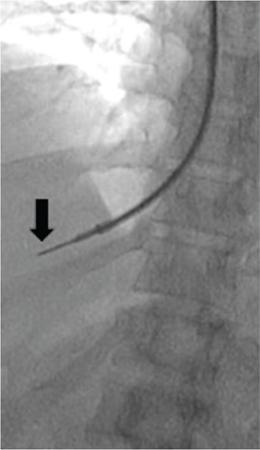

Amar Mukund, Shaleen Rana Portal hypertension (PH) is an inevitable complication of chronic liver disease. Chronic liver disease results in increased vascular resistance due to fibrosis and increased sinusoidal tone. Associated increase in portal flow is seen due to hyperdynamic circulation and expanded plasma volume which is a result of splanchnic vasodilatation and neoangiogenesis. Splanchnic vasodilatation further activates the vasoactive pathways secondary to systemic underfilling, resulting in ascites and renal derangement. As the portal pressure increases there is a transition from the subclinical to the clinical phase. Increasing portal pressure causes a gradient between the portal vein and inferior vena cava (IVC) known as the portal pressure gradient (PPG). The increasing gradient coupled with neoangiogenesis opens up portosystemic collaterals and formation of varices. The asymptomatic stage is called compensated cirrhosis (CC) or compensated advanced chronic liver disease. The patients with hepatic venous pressure gradient (HVPG) between 5 and 10 mm Hg are labelled as mild PH while those with HVPG >10 mm Hg are labelled as clinically significant portal hypertension (CSPH). The onset of CSPH is associated with various complications of PH. The causes of PH have been classified into (1) Prehepatic (portal, splenic or mesenteric vein thrombosis), (2) Intrahepatic (diseases like viral/alcoholic hepatitis) and (3) Posthepatic (Budd–Chiari syndrome). Complications of PH like ascites, encephalopathy and variceal bleeding increase the morbidity and mortality in patients with chronic liver disease and are directly proportional to the increasing portal pressure. Early recognition and diagnosis of PH and its types can help to prevent development of complications in an asymptomatic patient and to treat the complications in a symptomatic patient. Subclinical PH usually has no positive signs on examination. Presence of splenomegaly, abdominal wall collaterals, ascites and spider naevi suggest advanced disease. Various parameters like albumin, international normalized ratio (INR), platelets and liver function tests have been used in various combinations (Fibroindex, AST – platelet ratio index and Fibrosis – 4) and attempts have been made to correlate with progression of fibrosis and PH with reasonable degree of success. Ultrasound and contrast-enhanced CT/MRI are good in depicting the complications of chronic liver disease however none of the modalities measures the HVPG and do not correlate well with HVPG. TE can be used as a tool for assessing liver stiffness in patients with chronic liver disease. Baveno VI consensus workshop recommends that TE values >15 kPa suggests CC and screening endoscopy can be avoided in patients with liver stiffness <20 kPa and platelet count >1,50,000 as these patients have very lower risk of varices. The above-mentioned noninvasive modalities lack the sensitivity and specificity of HVPG and none of these modalities directly measure the HVPG. HVPG is an invasive technique which helps in determining portal pressure using a catheter placed in one of the hepatic veins. When a catheter is wedged in the hepatic vein the proximal column of blood reflects the pressure within the hepatic sinusoids. In cirrhosis, there is loss of normal connections within the sinusoids and the wedged hepatic venous pressure (WHVP) represents the portal pressure. Hepatic vein pressure gradient (HVPG) is calculated by subtracting free hepatic venous pressure (FHVP) from the WHVP. HVPG measurement is currently considered the gold standard for measurement of portal venous pressure in chronic liver disease. HVPG is helpful in diagnosing and measuring the severity of PH. HVPG predicts the severity of cirrhosis, clinical course in chronic hepatitis B and C infections and the development of complications. It is a surrogate clinical marker and has been used for prognostication and treatment response. HVPG >10 mm Hg is associated with formation of oesophagal varices while HVPG >12 mm Hg is associated with increased risk of variceal bleeding and ascites. A baseline HVPG of ≥16 is associated with increased risk of death irrespective of presence or absence of varices with no bleeding. Patients with HVPG ≥20 mm Hg presenting with variceal bleeding are more likely to have early rebleeding or inability to control bleeding than patients with HVPG <20 mm Hg. There is a higher transfusion requirement, longer intensive care unit stay and increased mortality in patients with HVPG ≥20 mm Hg. Decrease in HVPG to ≤12 mm Hg with pharmacotherapy or improving liver functions prevents variceal bleeding and reduces the size of existing varices. Similarly, ≥20% reduction in baseline HVPG reduces the risk of bleeding, variceal rebleed, ascites and mortality. Serial measurements of HVPG have been used for assessment of response to Hepatitis C treatment and effect of pharmacological therapy in lowering portal pressure. Several studies showed that there was significant reduction in HVPG posttreatment for hepatitis C infections. Preoperative use of HVPG in patients undergoing hepatectomy has been found to predict post hepatectomy decompensation and is more likely to occur in patients with CSPH (HVPG >10 mm Hg). HVPG also predicts recurrence or onset of hepatitis C cirrhosis in transplant patients and HVPG >6 mm Hg in these patients is associated with disease progression. HVPG measurement via hepatic vein catheterization is simple, safe and reproducible technique with immense clinical benefit. Hepatic vein catheterization is done under conscious sedation in a daycare setting with continuous monitoring of the vitals during the procedure. The patient should be fasting for minimum 6 hours. Venous access (Internal jugular, femoral or ante cubital vein) is secured under local anaesthesia. A balloon-tipped catheter is advanced into the right hepatic vein through the internal jugular vein (IJV) or IVC over a guidewire. Contrast is injected through the balloon catheter to confirm the position of the catheter and the diameter of the vein. FHVP is measured by letting the catheter tip float freely in the hepatic vein for at least 15 seconds within 5 cm of the hepatic vein ostium. WHPV is measured by inflating the balloon so that it is well opposed to the venous walls and the pressure tracing is stable for a minute (Fig. 9.26.1). After measuring the pressure adequate occlusion of the vein is confirmed by injecting 3–5 mL contrast slowly which should result in a wedge sinusoidogram, no reflux via collateral veins, absence of venous waveform and no blood on applying suction through the catheter. In the event of inadequate occlusion, the pressure is measured again and occlusion is verified again. Three readings are taken if the variation is ≤1 mm Hg and a mean of the values is considered. Permanent recording of the tracing using a multichannel recorder is done. The HVPG is calculated by subtracting FHVP from the WHVP. The advantage of measuring the gradient is that it is unaffected by changes in abdominal pressure, ascites or the hydration status of the patient. Venous pressure should also be measured in the IVC and the right atrium (RA). The IVC pressure should be measured at the level of the hepatic vein ostia because the pressure may be higher inferiorly due to compression of the IVC by hepatic parenchymal hypertrophy. The gradient between the hepatic veins and the RA should not be more than 2 mm Hg. If the gradient is >2 mm Hg then one must suspect a narrowing or a web in the hepatic vein or the IVC. Using RA pressures for HVPG measurement has the advantages of easy reproducibility and that it measures the actual portosystemic gradient. WHVP should be separately mentioned as it represents the pressure of blood in the varices and hence risk of variceal rupture. Patients coughing, movement or talking should also be recorded as it may cause artefacts while recording a trace. After successfully measuring the pressures the catheter and the sheath is removed and manual compression of the puncture site is done till the oozing stops followed by immobilization of the part for at least 4 hours. Some points to be kept in mind while measuring HVPG. HVPG measurement is a safe procedure with no major complication or mortality. Puncture site leakage and hematoma of the access vessel are the common complications. Rare complications are vasovagal syncope and arteriovenous fistula formation. Most of the complications can be avoided by using ultrasound for puncture of the access vessels and adequate postprocedural compression. Self-limiting supraventricular arrhythmias may be seen when the wire or the catheter traverses the RA. TJLB was introduced to reduce the complications associated with percutaneous liver biopsy (PLB) in patients with ascites, coagulopathy or in patients whose percutaneous biopsy had failed. Transjugular biopsy is now an acceptable and established technique for obtaining biopsy from the liver with no incidence of major complications. TJLB is done as a daycare procedure. Patient has to be fasting for 6 hours and an informed consent should be taken. The patient is shifted to a procedure room/cath-lab and the right neck is cleaned and draped. Continuous monitoring of the vitals is done throughout the procedure. Under local anaesthesia right IJV is accessed and a 10 F vascular sheath is introduced. Through the sheath, right hepatic vein is accessed using a 5F catheter and J tip floppy guidewire (Terumo, Japan). A contrast run is taken to confirm the position of the catheter in the right hepatic vein. The floppy guidewire is exchanged with a 0.035-inch stiff guidewire over which a curved stiff TJLB cannula is advanced. The stiff TJLB cannula is wedged against the wall of the hepatic vein. Wedging prevents the needle from slipping while taking a tissue core. This is followed by introduction of the semiautomatic coaxial biopsy gun (Fig. 9.26.2). Two to three cores are taken. The needle should be directed anteriorly when taking a biopsy from the right hepatic vein and laterally while taking biopsy from the middle hepatic vein. A contrast run is taken postprocedure. Postprocedure the neck access site is compressed manually and patient is monitored for 4–6 hours. If patient complains of severe pain not relieved by analgesics or if there is any tachycardia/fall in blood pressure, ultrasound should be done to rule out hemoperitoneum. Following important steps not to be overlooked.